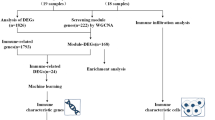

The row chart of the study is described in Fig. 1.

Schizophrenia (SCZ) is a prevalent, severe, and persistent mental disorder with an unknown etiology. Growing evidence indicates that immunological dysfunction is vital in the development of SCZ. Our study aims to uncover potential immune-linked hub genes and immune infiltration characteristics of SCZ, as well as to develop a diagnostic model based on immune-linked central genes. GSE38484 and GSE54913 chip expression data for patients with SCZ and healthy controls were retrieved. Weighted gene co-expression network analysis (WGCNA) was performed to identify major module genes and critical immune-linked genes. Functional enrichment analysis was conducted to elucidate the involvement of key genes in the immunological response to SCZ, along with the examination of their protein interactions. Moreover, 202 peripheral blood samples were examined using the single-sample gene set enrichment analysis (ssGSEA) method to detect distinct immune cell types. Hub immune-linked genes in SCZ were identified using the minimal absolute contraction and selection operator analysis. Receptor profiles of central immune-linked genes were analyzed to distinguish the two groups. Finally, the association between immune-linked hub genes and various types of immune cells was assessed. Our findings revealed ten immune cell types and nine key genes involved in SCZ, including effector memory CD4+ T cells, activated CD8+ T cells, mast cells, naive CD8+ T cells, PBMC, type 17 helper cells (Th17), central memory CD8+ T cells, CD56 bright NK cells, memory B cells, and regulatory T cells. Diagnostic models constructed using LASSO regression exhibited an average area under the curve (AUC) of 0.866. Our results indicate immunological dysfunction as a factor in the development of SCZ. ASGR2, ADRM1, AHANK, S100A8, FUCA1, AKNA, GATA3, AHCYL2, and PTRH2 are the key regulatory genes of immune cells, highlighting their potential as novel therapeutic targets for SCZ.

In this study, we employed bioinformatics techniques to identify potential immune-linked hub genes and immune infiltration modes of SCZ. We performed WGCNA to identify module genes and obtained a collection of immune-linked genes specific to 28 different types of peripheral immune cells (Supplementary Table 1) (Charoentong et al. 2017). Functional enrichment and protein interaction network analyses were performed on hub immune-linked genes obtained from the intersection of immune-linked genes and major module genes. Furthermore, we investigated the immune infiltration patterns using the single-sample gene set enrichment analysis (ssGSEA) algorithm and employed the receiver operating characteristic (ROC) curve analysis of immune-associated hub genes to discriminate patients with SCZ from controls. Our study also analyzed the interplay between immune-linked hub genes and distinct immune cell types. We further validated the expression of genes involved in immunological hub function using the GSE54913 dataset. The identification of key immune-related genes and immune infiltration characteristics in SCZ may provide valuable insights into potential therapeutic targets for the disorder.